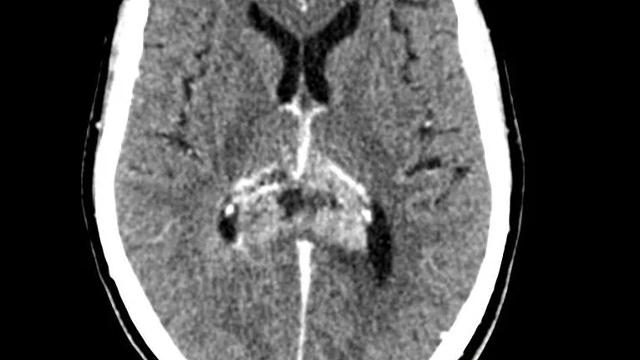

En CT-scanning er en undersøgelse, hvor der bliver taget en række røntgenbilleder hurtigt efter hinanden. Herefter bliver billederne bearbejdet i en computer. Denne teknik giver detaljerede billeder af hjernen, så lægen kan se, hvor og hvor dybt en eventuel tumor sidder.

Lægen vælger CT-scanning, hvis du ikke kan MR-scannes. Det kan f.eks. skyldes, at du har fået indopereret metal eller en pacemaker, der ikke tåler et magnetfelt.

Der laves som regel to sæt scanninger. Ét uden og ét med kontraststof, som bliver sprøjtet ind i en blodåre. Kontraststoffet gør det nemmere at se tumorer, betændelse og blodkar. Læs mere om undersøgelsen: